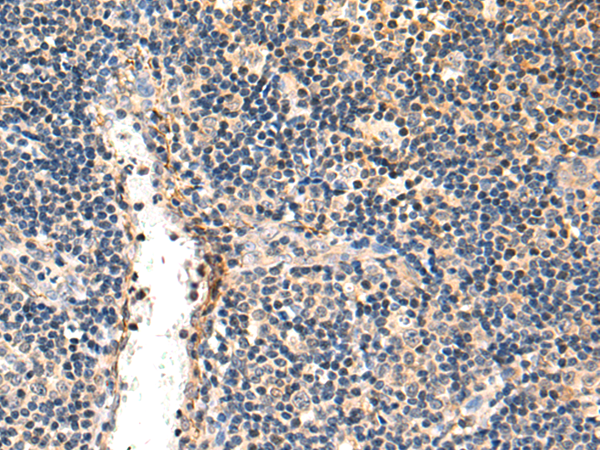

分类: 科研抗体货号: P07450别名: MIC-A; PERB11.1应用: WB,IHC反应种属: Human